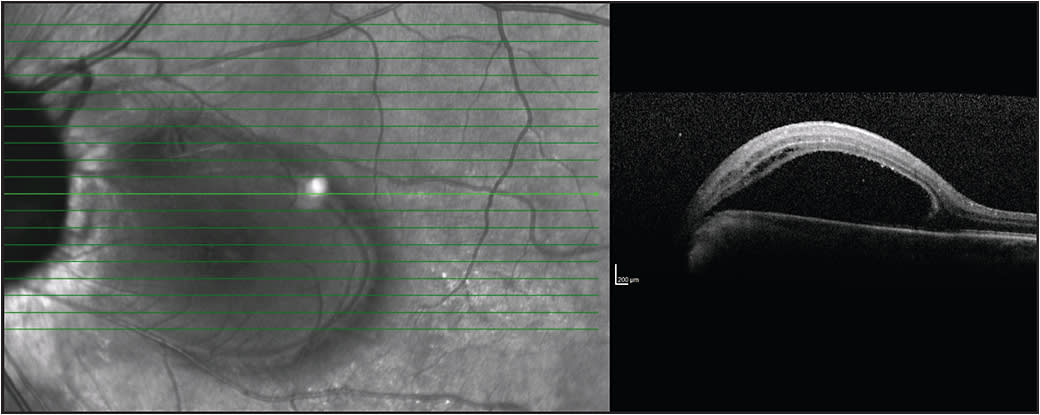

Figure 4. A) Preoperative OCT of right eye revealing subretinal fluid. B) Same patient one month postoperatively with decreased amount of subretinal fluid. C) Same eye seen six months postoperatively showing further diminishing of the subretinal fluid. D) Fifteen-month follow-up with complete macular reattachment.

In 2015, Rayat et al published a retrospective, multicenter trial that assessed surgical success utilizing a variety of techniques for ODP maculopathy.23 Thirty-two eyes were included in the final analysis. All of the eyes underwent PPV with triamcinolone-confirmed PVD with or without adjuvant treatments (gas tamponade and/or ILM peeling and/or temporal endolaser).

Foveal reattachment occurred in 81% of eyes postsurgery at a median time of 416 days. Ten of 34 eyes required reoperation, and the average time to the second surgery was 404 days. VA improved from a mean preoperative level of 20/185 to a final VA of 20/63. Success rates were not affected by ILM peeling, temporal laser at the disk margin, or type of gas utilized (air, SF6 or C3F8).23

These results suggest that laser and ILM peeling may be unnecessary for patients with ODP maculopathy. Surgeons should consider the potentially harmful effects of laser at the disk margin, as well as ILM peeling.

Complete separation of the vitreous from the optic nerve and macula appears to be of primary importance for surgical success with no improvement in success when using adjuvant therapies (laser, ILM peeling, and/or gas tamponade).

The authors recommend triamcinolone staining of the vitreous to confirm complete separation from the retina and identification of any residual vitreous. Removal of this traction by vitrectomy and surgically induced PVD allows the RPE pump to reabsorb subretinal fluid, reattaching the retina and thereby improving VA.